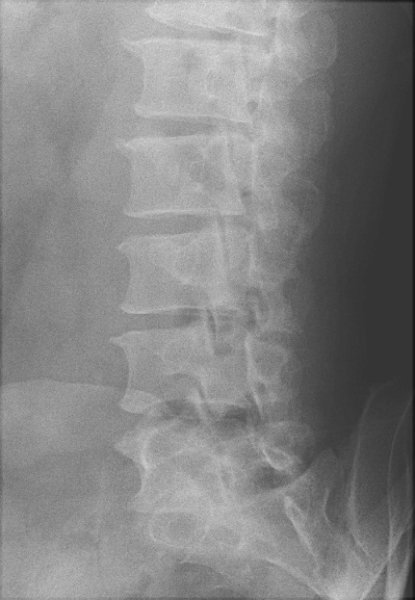

Return to Spondylolysis